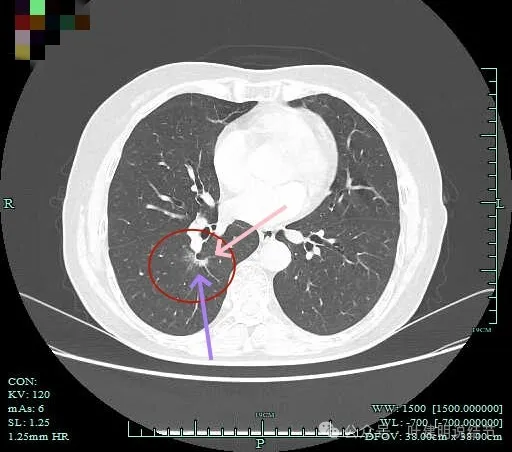

病灶影响到斜裂肺门部,边缘毛刺明显。灶内支气管僵硬。

密度杂乱,毛刺明显,支气管僵硬。

杂乱密度,整体轮廓较清,边缘毛糙。

斜裂根部有增厚并与病灶连着。考虑是肿瘤已经侵及叶间裂。

病灶边缘毛刺明显。